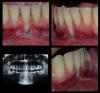

Desna911 Опубликовано 5 марта, 2013 Поделиться Опубликовано 5 марта, 2013 Подскажите пожалуйста будет ли какая то польза от операции при такой рецессии (см. фото)? Рецессия произошла в результате травмы. Планируется пересадить кусок с неба, а также будет использоваться какой то материал компании geistlich. Цена операции, примерно 20000 руб. Ссылка на комментарий

Sahan Опубликовано 5 марта, 2013 Поделиться Опубликовано 5 марта, 2013 Пересадить трансплантат с неба, возможно 2 раза с перерывом 6 мес. Прогноз хороший. Ссылка на комментарий

IvanK Опубликовано 5 марта, 2013 Поделиться Опубликовано 5 марта, 2013 (изменено) Я про "материал", лучше с неба, бугра в.челюсти.Рассчитывайте на 2- 3 операции Изменено 5 марта, 2013 пользователем IvanK Ссылка на комментарий

IvanK Опубликовано 5 марта, 2013 Поделиться Опубликовано 5 марта, 2013 1) А биометериал обязательно использовать? Какая у него функция в такой операции?2) Нужно ли делать ультразвуковую чистку перед вмешательством?3) В случаи неудачи ситуации не усугубится?4) Если этот зуб выпадет, что можно будет сделать?Нет. Меньше брать с донорской зоны.Лучше снять зуб.отложенияПри соблюдении протокола, нетКостная пластика + имплантация. Ссылка на комментарий